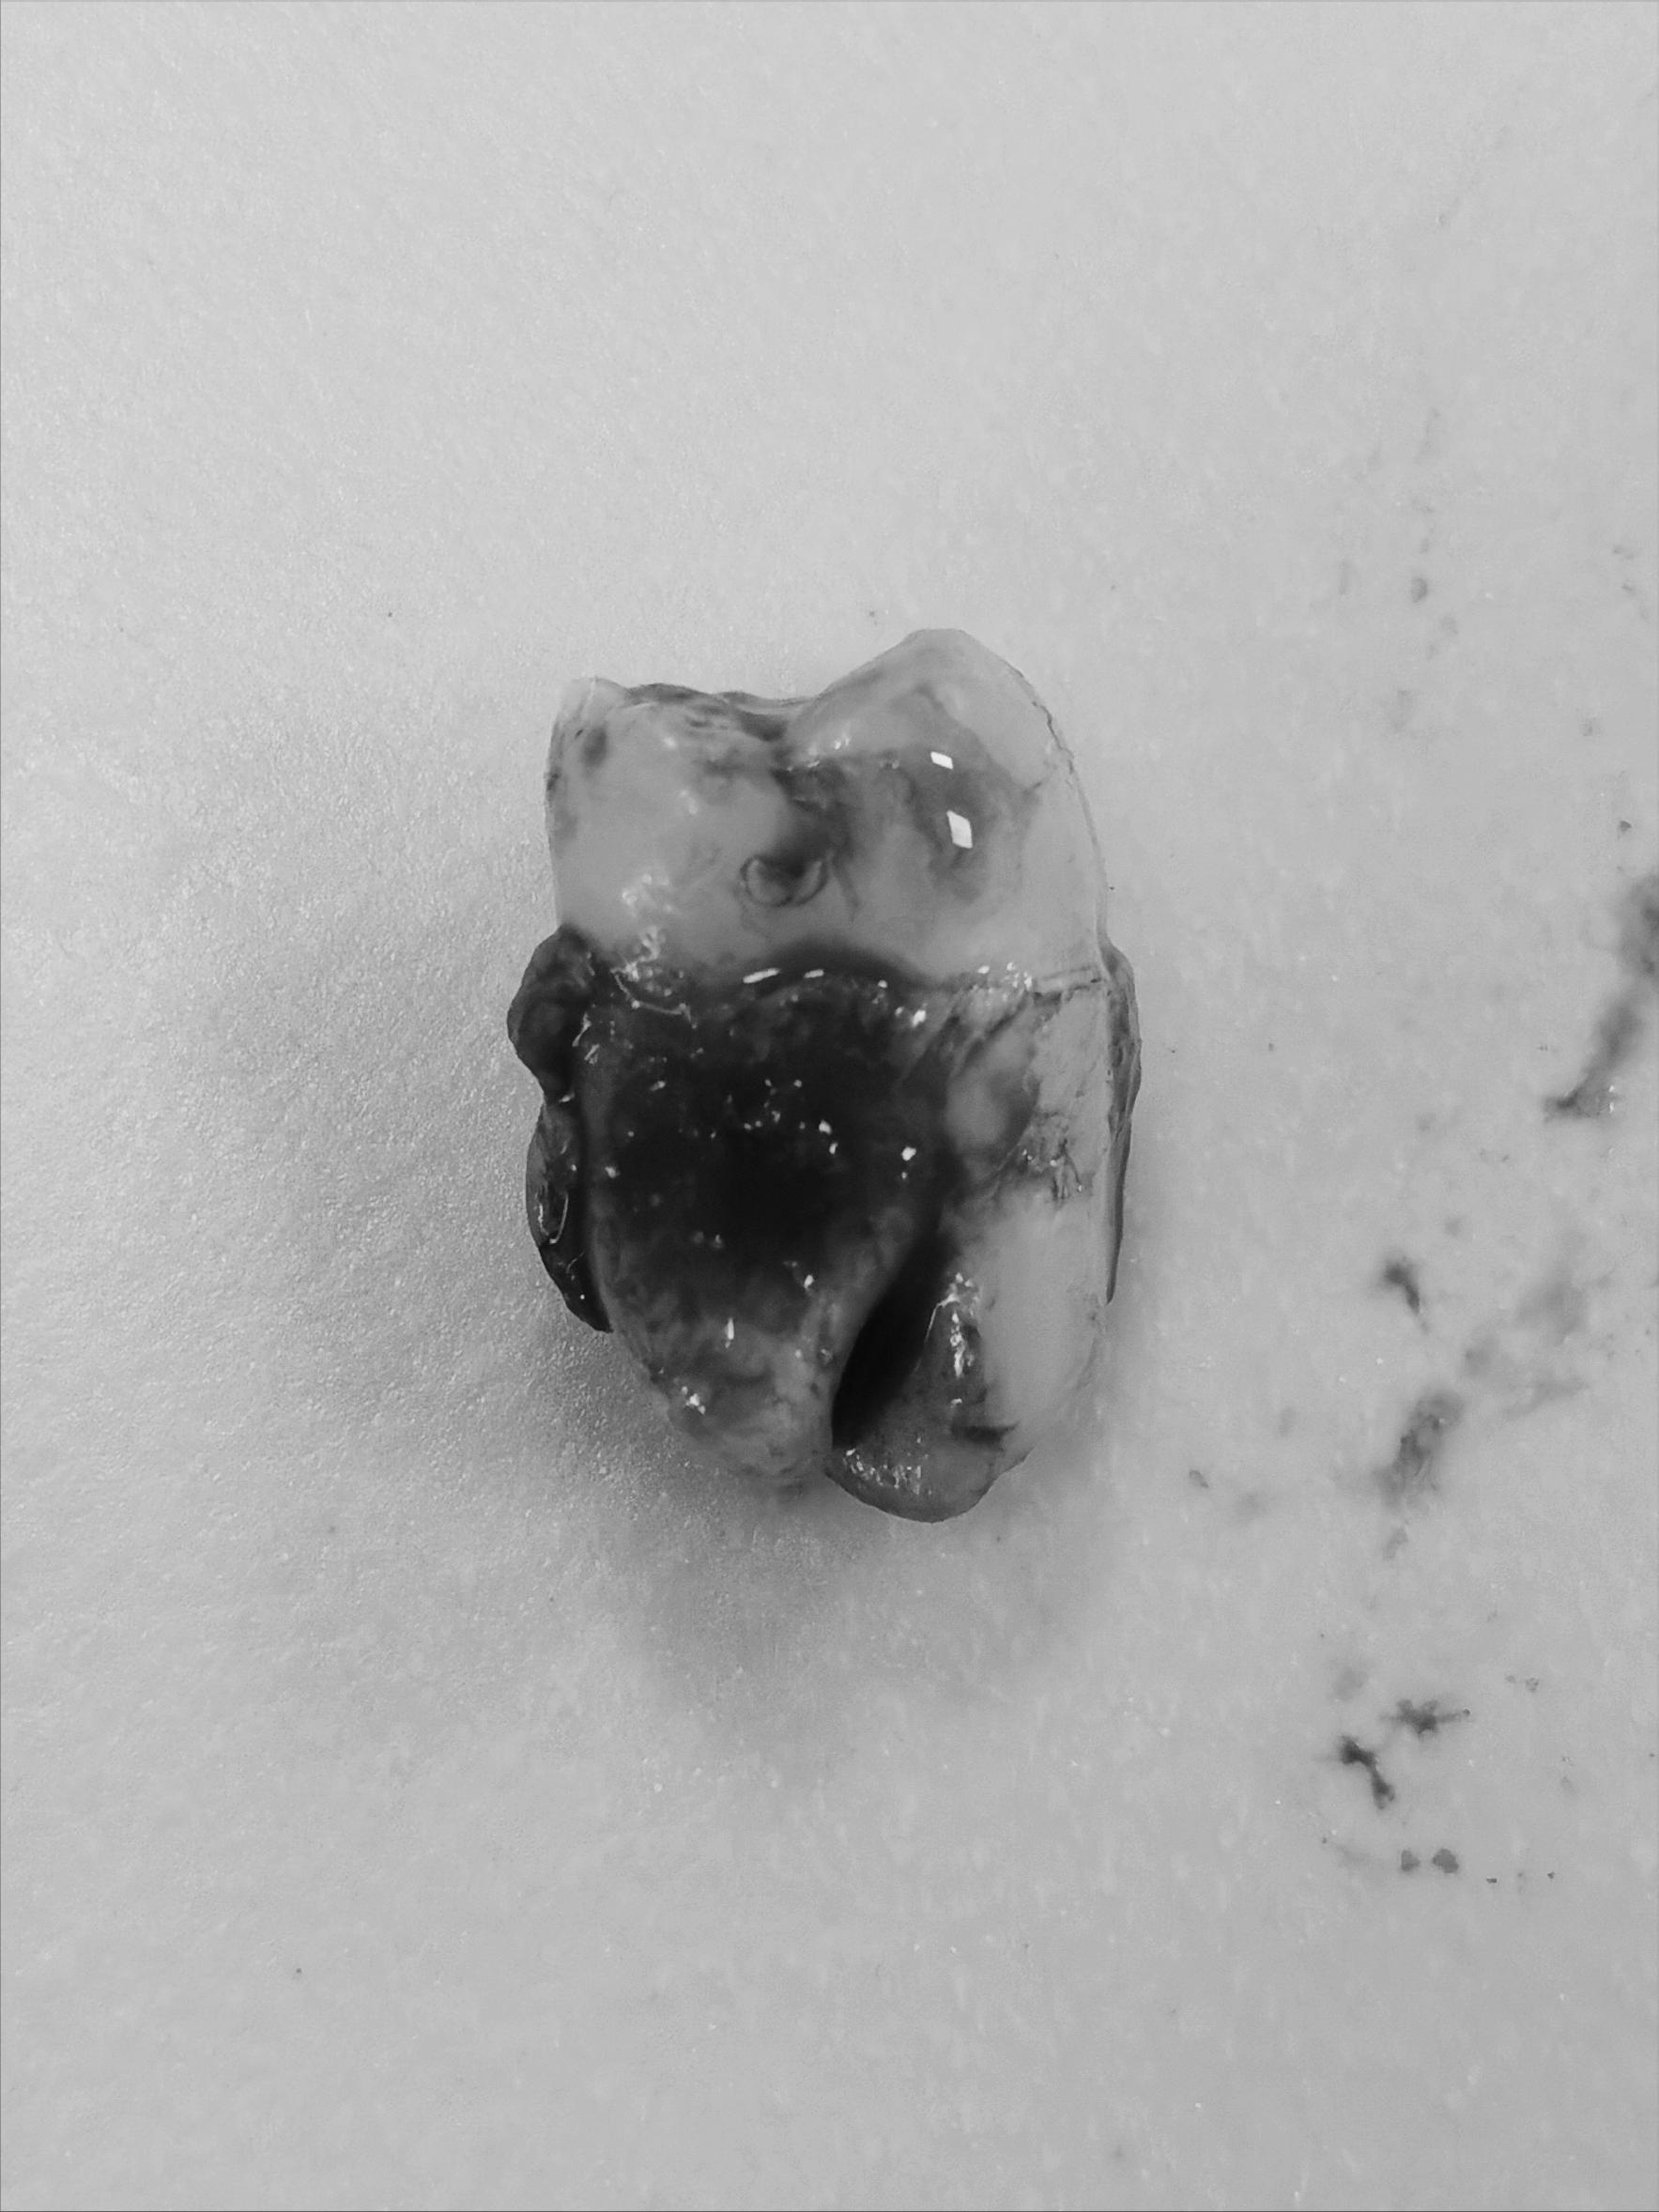

拔下来的牙齿有些地方可以让带走,但正常是属于医疗废料,医生最多让我拍照留念了下就拿去处理了。1号智齿拔除一共消费524.44元。这么看牙医确实高效挣钱...就拔了五分钟...一切都很顺利,医生给了我个冰袋冷敷半小时,咬住一个海绵等四十五分钟后吐掉,创口没有再流血就算结束了,后续就是等创口自愈,没有吃药没有症状,麻药过了也没什么痛感,总体算是无痛拔牙...但下一次拔牙就没有这么好运了...